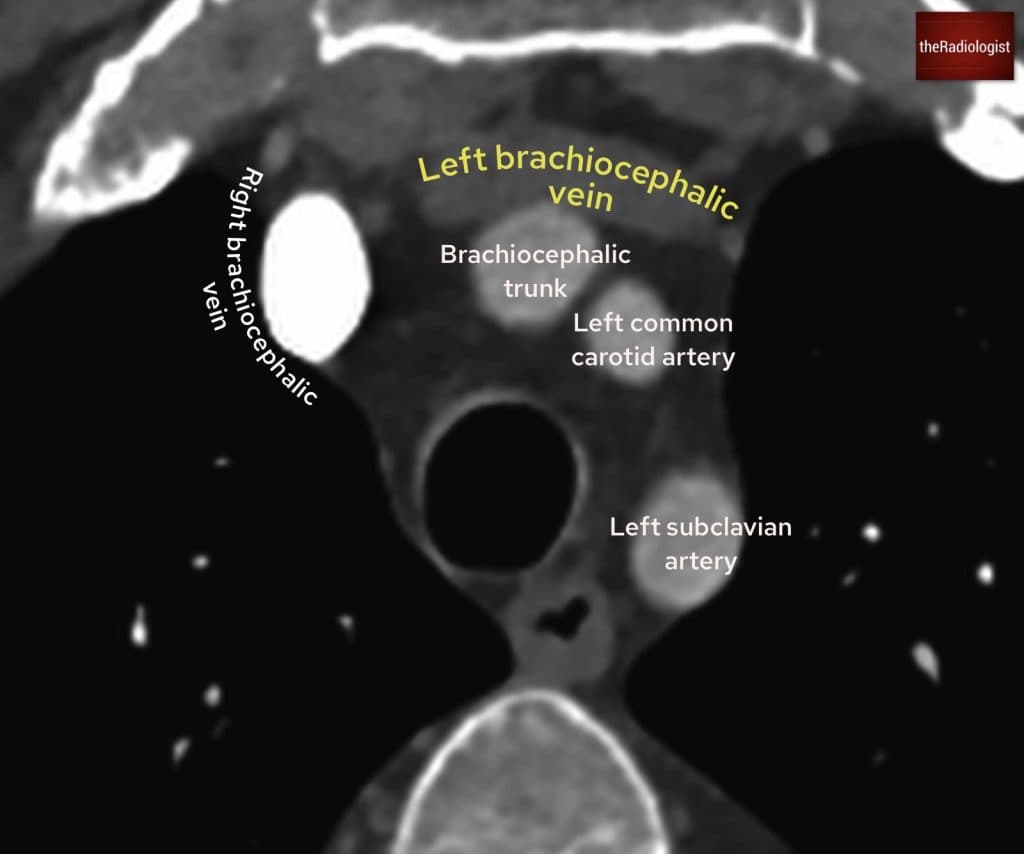

Follow the contrast from the subclavian vein into the brachiocephalic vein on either the left or the right. This will then feed into the superior vena cava and into the right atrium. On a CTPA study, this should appear bright. The contrast will then pass through the tricuspid valve into the right ventricle.

Here we see the left and right brachiocephalic veins at the level of the branches of the arch of aorta.

Follow the brachiocephalic veins into SVC and then down into the right atrium. From here you can follow the contrast through the tricuspid valve into the right ventricle.